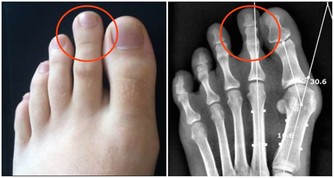

*****日常生活習慣*****●儘量避開碳酸飲料、加工食品

可樂等碳酸飲料及快餐等加工食品含有大量的磷,會妨礙人體吸收鈣,不利骨骼健康。